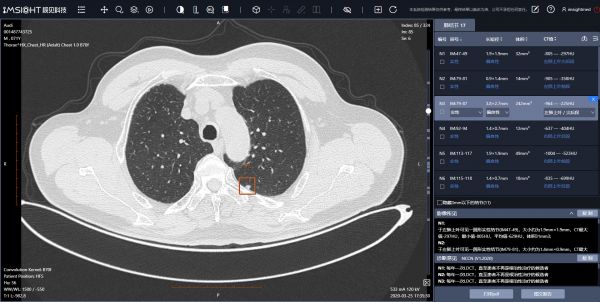

首先要解决产品的问题。最初各企业的影像AI产品几乎都聚焦在CT肺结节,后来陆续推出了胸部DR、骨折、脑卒中、冠脉、乳腺钼靶等系列产品,但总体来说应用最广、功能最为成熟的还是肺结节。在解决更多病种,提高准确性、拓宽功能以及提升应用体验方面,还有很大提升空间。其次是政策,包括像NMPA(National Medical Products Administration,即国家药品监督管理局)的审批、临床的应用规范、收费目录的审批、医保准入等等,也还有比较长的路要走。

初期的时候,大家的工作重心都是快速做出产品,所以做影像科的都在做CT肺小结节,做眼科的都在做眼底视网膜糖筛。主要是因为肺癌是全球发病率和死亡率最高的癌症病种,影像检查方法比较一致,前期算法、数据积累都比较多,问题也清晰。这个阶段,大家基本都是先产品后场景,先做出产品,再去推广。后面大家就开始慢慢先考虑需求和场景,然后再做产品,所以各个厂商后续推出的产品差异化就出来了,每个方向都有。

CT肺结节辅助筛查系统

在企业定位和产品布局方面,各家AI企业做出了不同的选择,总体上来说分“纵向策略”和“横向策略”两大类。拿我们自己来说,我们的核心竞争力是对AI算法的开发,同时我们认为现阶段AI应该更善于解决医生容易遗漏的、数量极大的问题,而不善于解决对医生来说都是非常难以判断的问题,比如疑难杂症。所以我们在产品方向上聚焦于筛查类项目,并不断扩大可覆盖的病种范围。